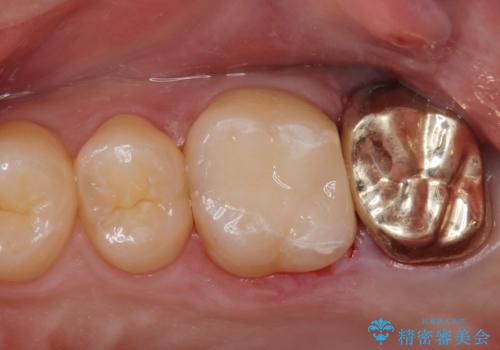

- PGAクラウン・仮歯 13.2万円 精密根管治療・コア 16.5万円 e-maxインレー 7.7万円費用は治療当時の料金となります

適合の良い被せ物が入りました。

ゴールドの被せ物は適合がよく虫歯の再発のリスクが低くなります。